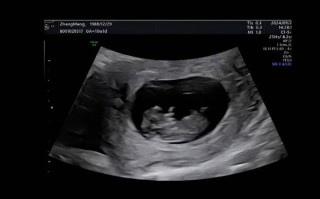

孕期B超报告单上的字母代码究竟是什么含义?新手爸妈该如何快速读懂这些数据? 孕期健康知识

孕期B超报告单上的字母代码究竟是什么含义?新手爸妈该如何快速读懂这些数据?

基本参数这部分是每次B超都会检查的基础数据,BPD ( Biparietal Diameter - 双顶径含义:测量胎儿头部两侧顶骨之间的距离,作用:这是评估胎儿大小和孕周最常用的指标之一,通过B...